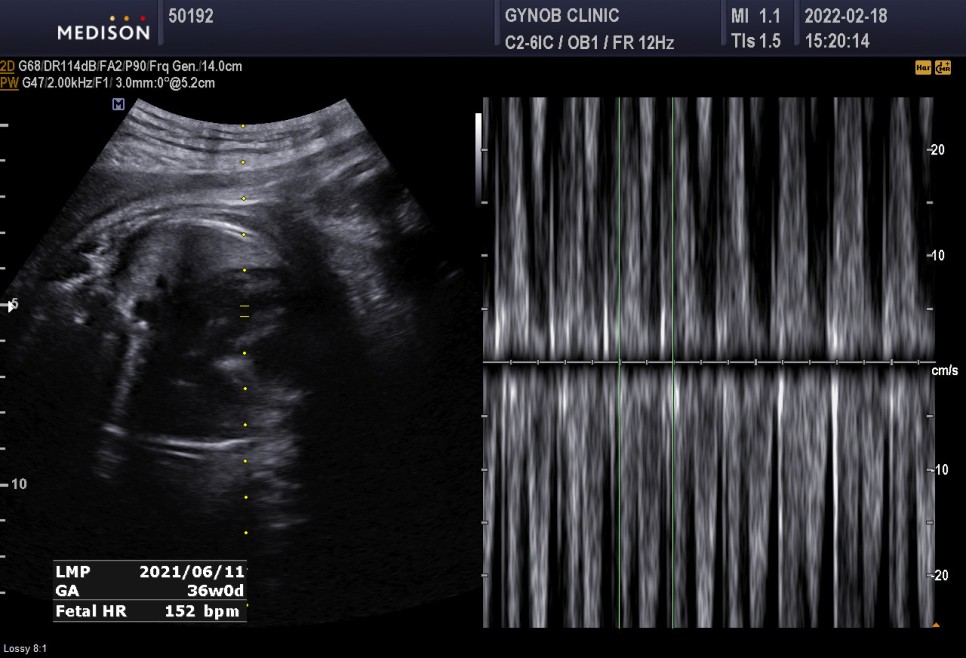

▲초음파실에서 초음파도 봤다=심상덕 원장님은 초음파를 5분 동안 꼬박꼬박 챙겨보신다.

아기의 머리 위치는 정상*경부 제대륜 1회 신경 쓸 필요는 없습니다.

- 경부 탯줄은 탯줄이 아기의 목 부분을 감고 있다는 것을 의미한다

쭉쭉 체중은 2.86kg 조금 더 큰 편.

심박수 152bpm 정상

태반과 양수의 정상

경부제 대륜 1번 탯줄에 목을 1번 감고 있다는 뜻이다.너무 신경 안 써도 될 것 같아